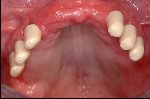

Vollkeramische Restauration auf eigenen Zähnen

- Vollkommen gesunde Situation des Zahnfleisches nach der Restauration mit vollkeramischen Kronen, keine schwarzen Ränder wie im Ausgangsbild (links) zu sehen.